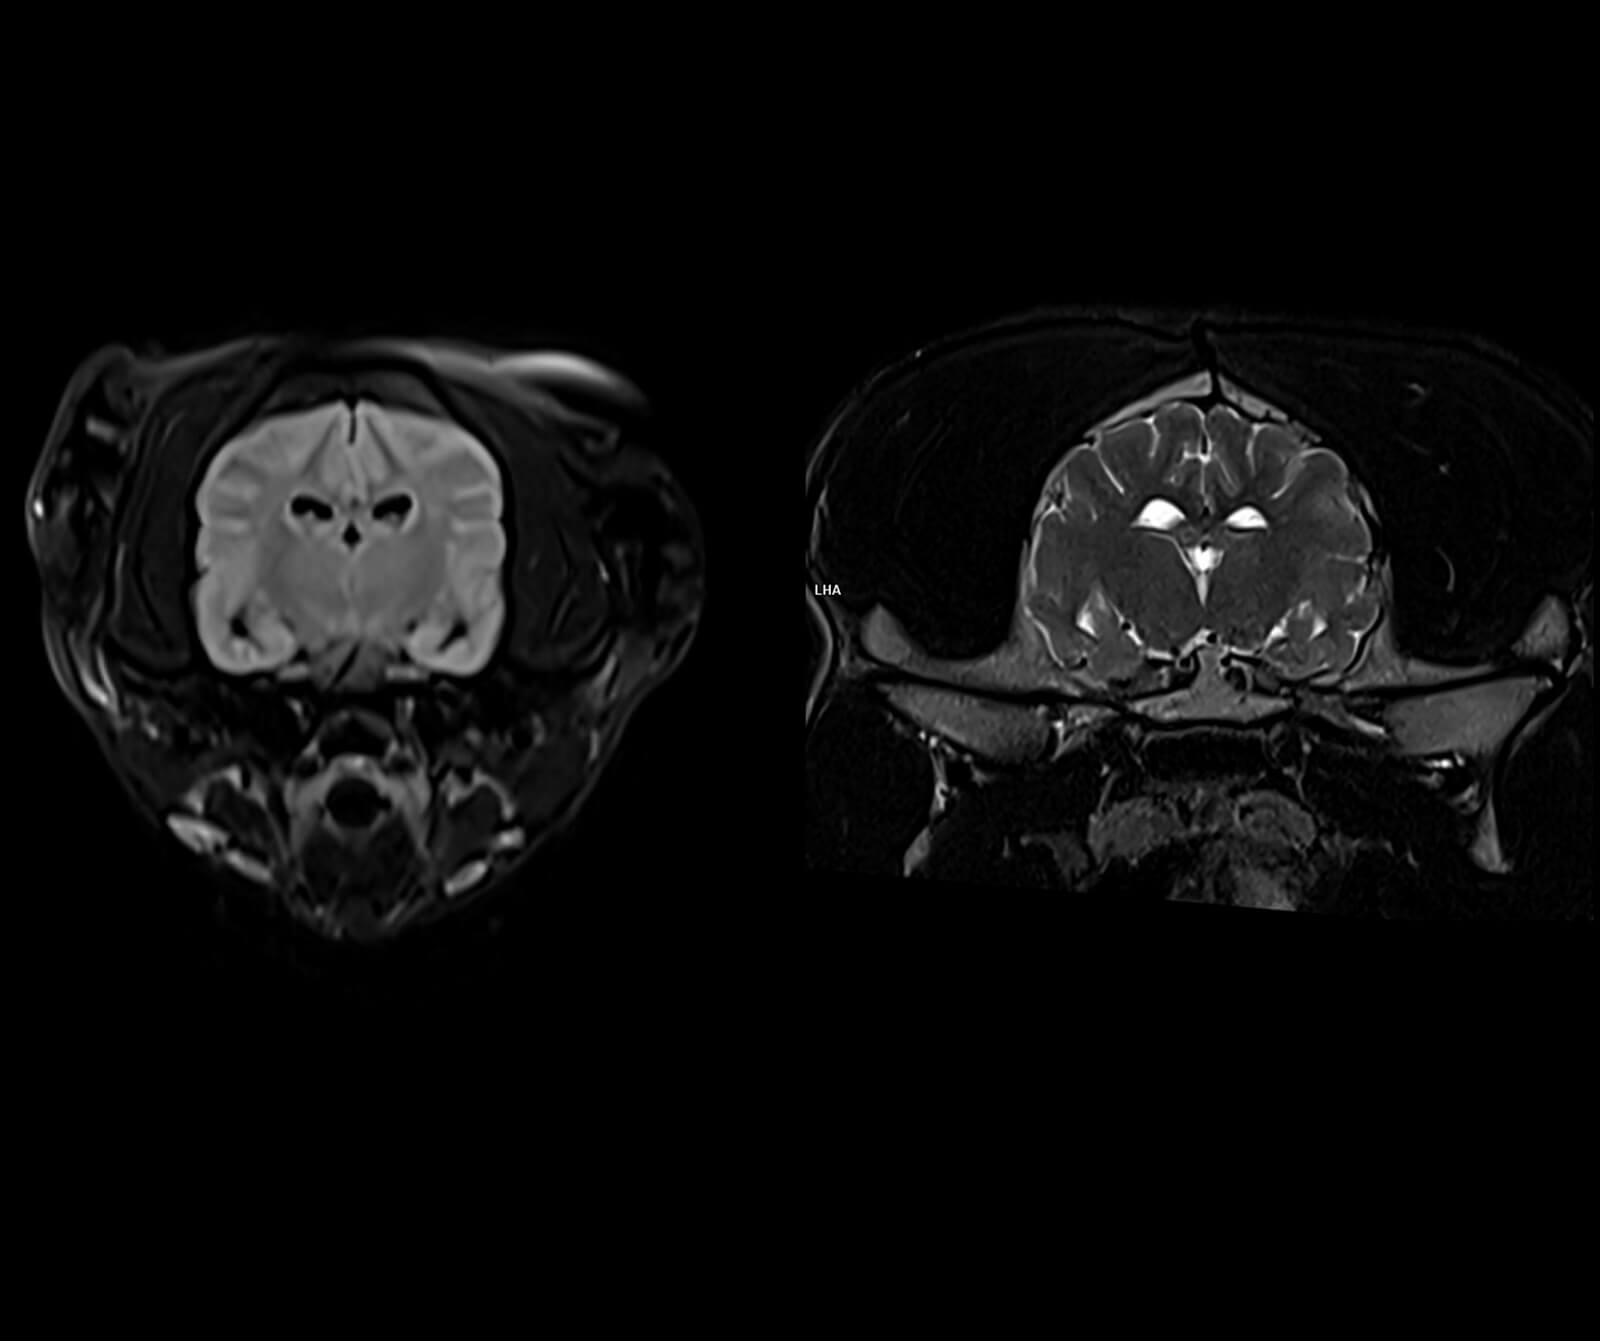

Manyetik Rezonans Görüntüleme (MR), sevimli dostlarımızın vücudundaki doku ve organların yüksek çözünürlükte, ayrıntılı ve güvenli biçimde değerlendirilmesini sağlayan ileri düzey bir tanısal görüntüleme yöntemidir. Radyasyon içermeyen bu yöntem, özellikle yumuşak dokuların detaylı incelenmesi gereken durumlarda en değerli tanı araçlarından biridir.

Veteriner hekimliğinde MR; beyin, omurilik, sinir sistemi, kas-iskelet sistemi ve iç organ hastalıklarının değerlendirilmesinde kritik rol oynar. Kemik yapılar dâhil olmak üzere vücudun tüm bölgeleri MR ile ayrıntılı şekilde incelenebilir.

• Beyin ve nörolojik hastalıkların değerlendirilmesi

Merkezimizde, süper iletken magnet teknolojisine sahip, yapay zekâ destekli Manyetik Rezonans (MR) sistemleri kullanılmaktadır. Veteriner hekimlik ihtiyaçlarına özel olarak optimize edilmiş bu ileri teknoloji sistemler; yüksek görüntü kalitesi ile hasta güvenliğini birlikte hedefleyen bir altyapı sunar.

Yapay zekâ destekli yazılım ve rekonstrüksiyon teknolojileri, görüntüleme sürecinin planlanması, ham verilerin işlenmesi ve görüntülerin yeniden oluşturulması aşamalarında aktif olarak kullanılmaktadır.